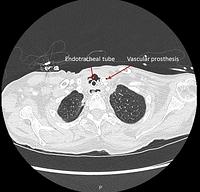

Tracheo-mediastinal fistula (CT scan)